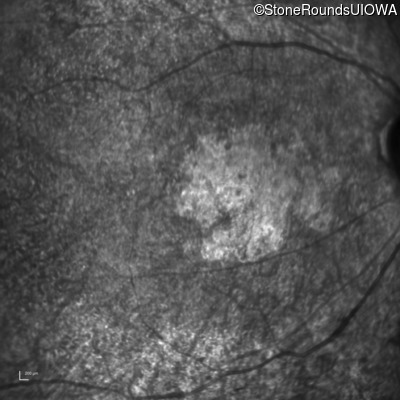

This 47 year old woman was born with a supernumerary digit on the ulnar side of both hands. As a young child, her best corrected visual acuity was completely normal. She had no difficulties with her vision until age 30 when her visual acuity could no longer be corrected to 20/20 and she began to notice some night blindness.

The clinical features supporting the diagnosis of Bardet Biedl syndrome in this patient include: bone-spicule-like pigmentation, narrowed arterioles and macular atrophy on ophthalmoscopy; photoreceptor loss on OCT; ulnar polydactyly, obesity, abnormal cognition, hypertension; and, normally sighted parents.